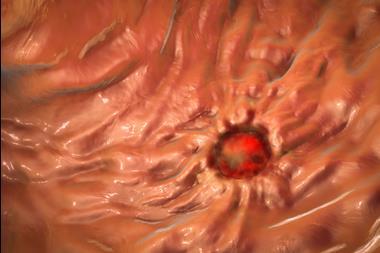

A potential alternative treatment for OA is the regeneration of cartilage from stem cells. However, not all types of stem cells can make cartilage and earlier clinical trials with mesenchymal stem or stromal cells (MSCs) did not convincingly demonstrate that MSCs make new cartilage when given to OA patients.

Although limb bud progenitors show promising results, they are not readily obtainable from humans. To overcome this, the scientists grew a high number of human pluripotent stem cells (hPSCs) in the lab, and after extensive protocol optimisation, they obtained hPSCs-derived limb bud progenitors. According to the gene and protein expression, these closely resembled their embryonic counterparts. The hPSC-derived limb bud progenitors also made new cartilage when transplanted into the knees of OA mice.